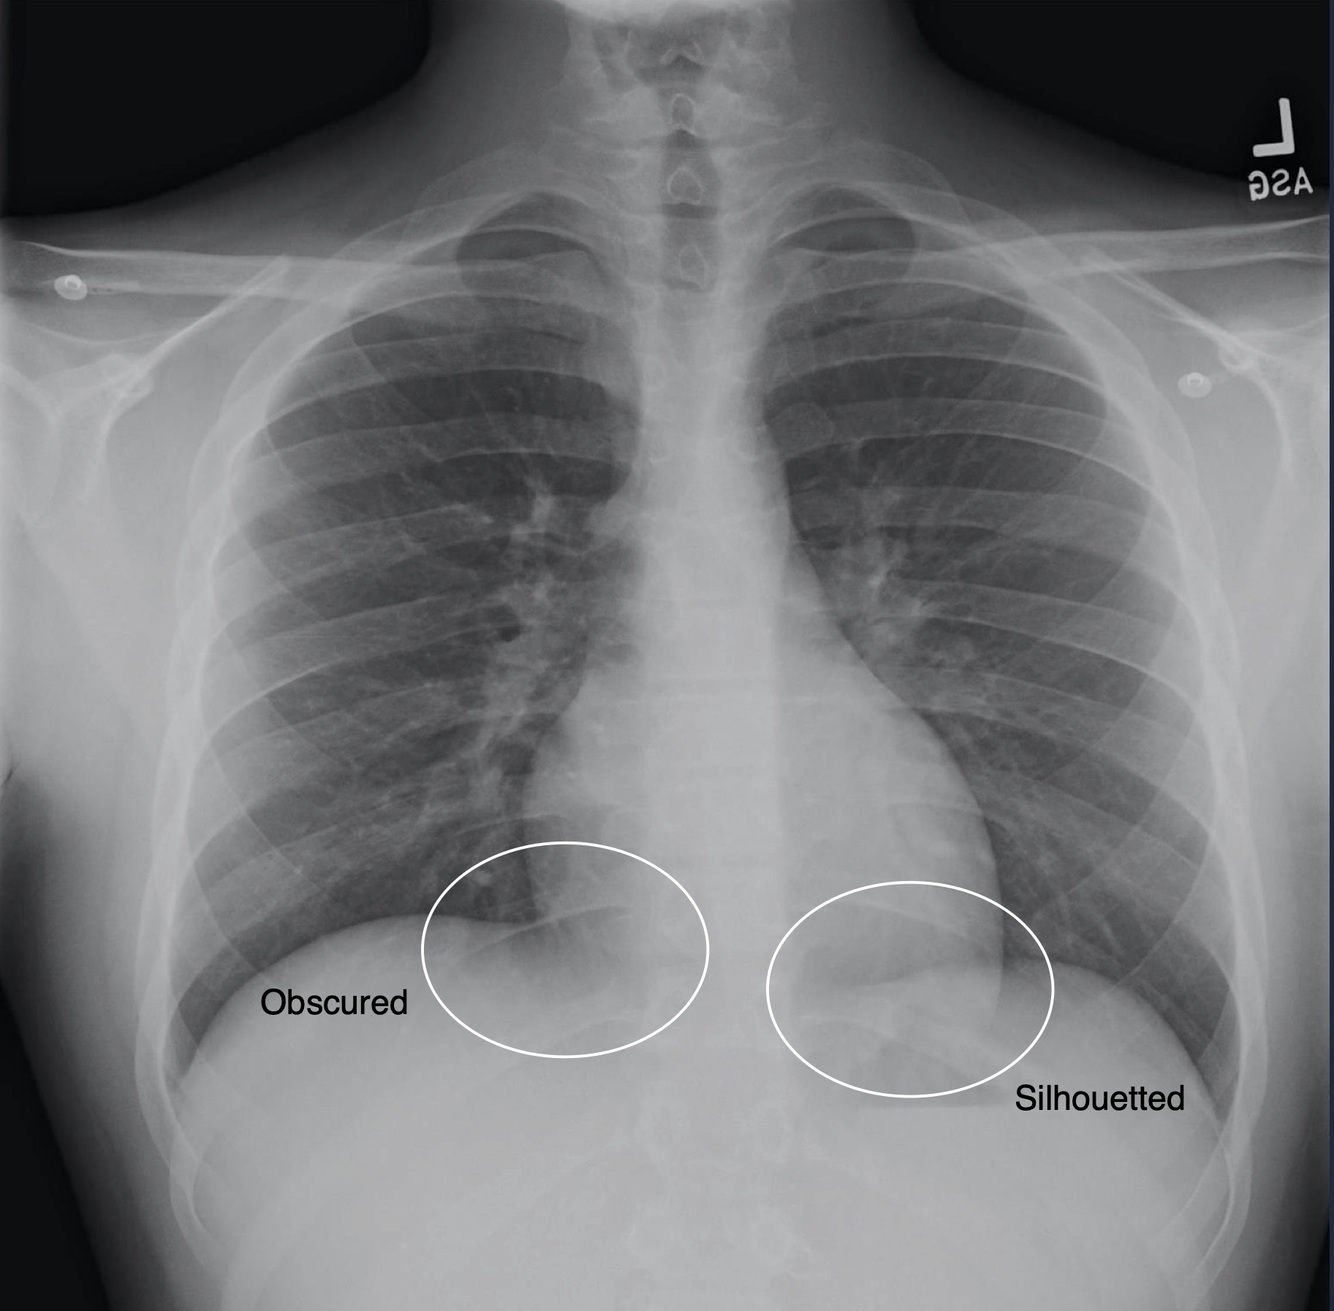

Obscured Margin

When two soft tissue densities lie in apposition, their borders will become indistinguishable or obscured.

Silhouette Sign

When two soft tissue densities overlap in an image but are seperated by air, their borders will still be visible.